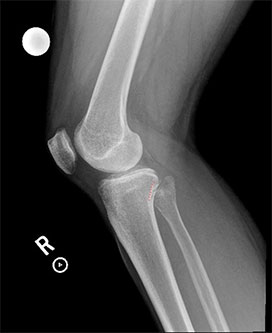

- Lateral and AP x-rays of the knee are often taken. On the lateral x-ray, the fibular head should be behind the posteromedial portion of the lateral tibial condyle known as the Resnick’s line. Displacement of the fibular head will disrupt this relationship. There are variable degrees of knee rotation on the lateral x-ray so an x-ray with 45-60 degrees of internal rotation is preferable for the PTFJ [5]. On the AP radiograph, half of the fibula head should be behind the lateral margin of the lateral tibial condyle. In an anterolateral dislocation the fibula will have less than half of its head overlapped. Axial computed tomography is the most accurate imaging to detect a proximal tibiofibular joint injury. Subtle proximal dislocations can be missed so comparison with the contralateral knee may improve detection.